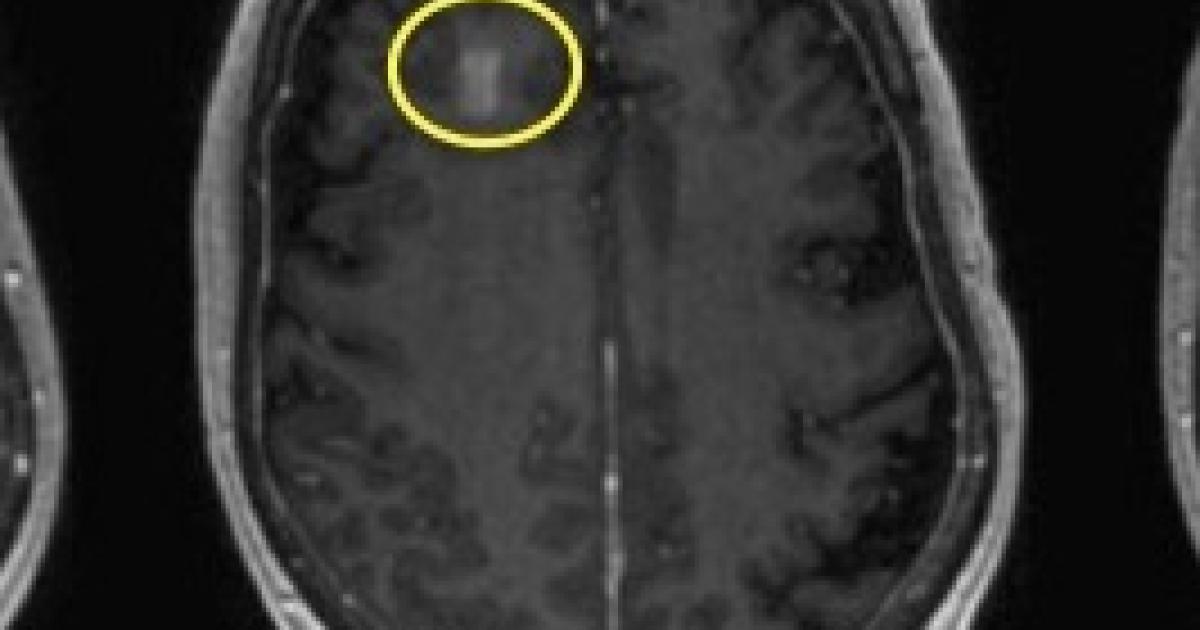

Scientists at the University of Toronto recently published the results of a Phase I safety trial in Nature Communications. Nir Lipsman and colleagues used a method called magnetic resonance-guided focused ultrasound (MRgFUS) in conjunction with injected microbubbles of air to temporarily open the BBB in five patients with early to moderate Alzheimer's disease (1). No adverse effects were observed.

MRI images of blood-brain barrier of one patient before, immediately after, and 24 hours following magnetic resonance-guided focused ultrasound. (a) Baseline MRI scan before procedure. (b) MRI scan immediately following the procedure. The yellow circle indicates the right frontal lobe, where a transient opening of the BBB is apparent. (c) The MRI scan 24 hours following the procedure shows that the BBB opening has closed. Source: Nature Communications volume 9, Article number: 2336 (2018)